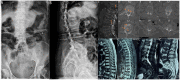

This study aimed to present a special case of treatment of a patient with multisegmental vertebral compression fracture, burst fracture, and sandwich vertebra and to review the literature on this condition. An 85 year-old female presented with severe low back pain but no radiating pain in the lower extremities. The patient was diagnosed with T12 and L5 vertebral compression fractures, fresh vertebral burst fractures in L2 and L3, and osteoporosis. The focus was on formulating a surgical treatment strategy. At the 12 month follow-up, no neurological deficits were observed, and the chosen surgical treatment approach yielded favorable clinical outcomes. A comprehensive literature review indicates that percutaneous kyphoplasty (PKP) can effectively alleviate pain and ensure safety in managing osteoporotic vertebral burst fractures. While complications remain a theoretical risk, they can be mitigated through meticulous assessment, careful surgical procedures, and appropriate preventive measures. PKP is an effective and safe treatment modality for osteoporotic vertebral burst fractures. Conservative management of sandwich vertebrae can yield positive clinical outcomes, but regular anti-osteoporosis treatment is necessary.